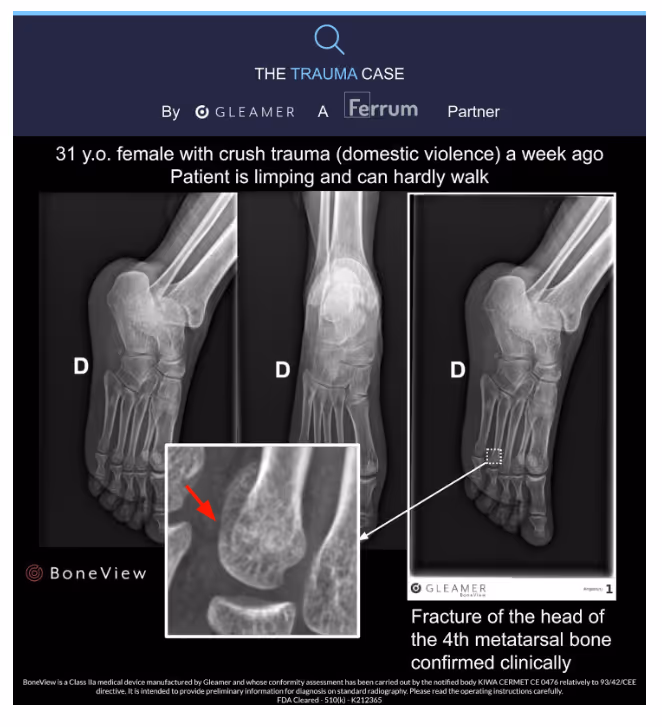

- A 31-year-old patient presented with a limp and was barely able to walk

- Fracture of the head of the 4th metatarsal bone detected by BoneView

- Fracture confirmed clinically